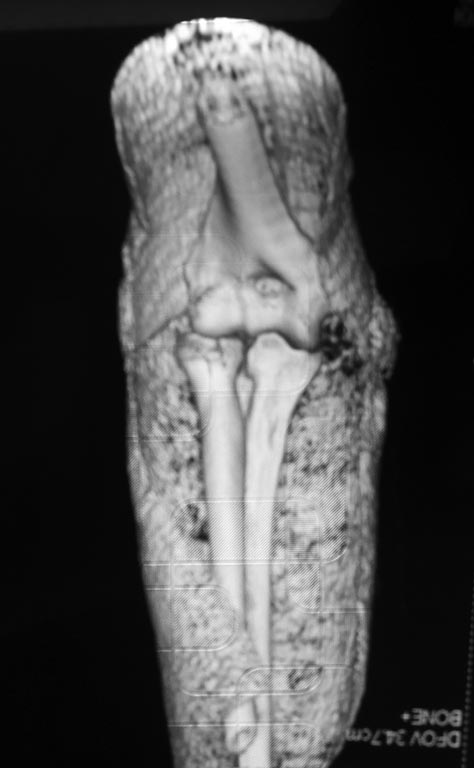

Судя по 3-Д КТ, перелом - много оскольчатый, но без смещения.

Синтезировать, или вообще не трогать. А 3D картинки дают мало информации. Лучше представляйте срезы в 3-х плоскостях.

Для выработки показаний достаточным бывают стандартные снимки, но иногда требуется косая рентгенограмма по Coyle. И для подтверждения смещений и оценки внутрисуставных фрагментов рекомендуется КТ, а 3D снимки показывают только поверхность, т.е. получается общая картина. МРТ дает возможность оценить состоянии связок.

В первом случае перелом Монтеджи, где доперационно сделано оценка положения головки к остальным элементам под рентгеном. Учитывая правильность взаимотношении произведена фиксация только локтевого отростка, Второй случай, заменена на протез, и третий, кроме фиксации головки - реконструкция capitellum латерального мыщелка.